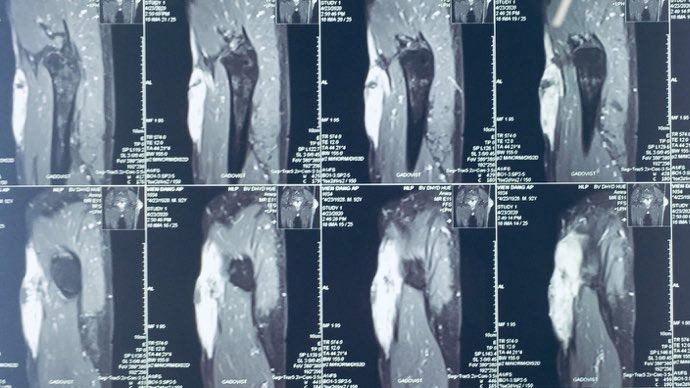

Ứng dụng kỹ thuật đồng trục có nút tắc đường hầm trong sinh thiết lõi tổn thương lách

(COAXIAL CORE NEEDLE BIOPSY WITH TRACK EMBOLIZATION OF THE SPLENIC LESIONS)